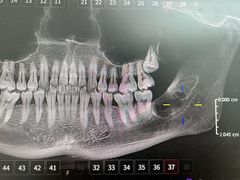

• -牙博士口腔品牌连锁(杨浦店)

panda | 25-11-13

报错